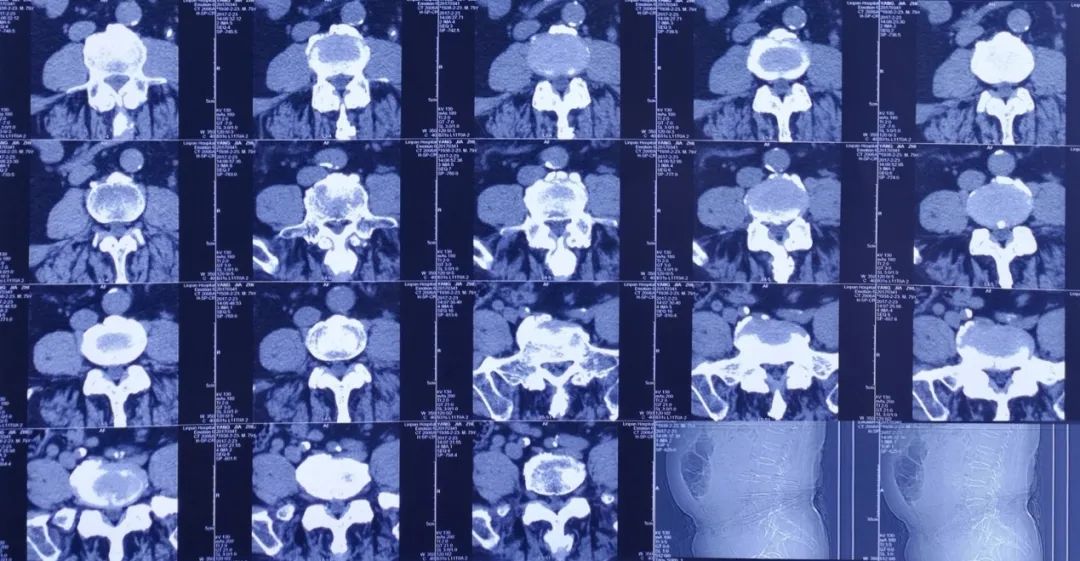

术前CT

术前MRI

术前诊断:1.胸腰椎后凸畸形,2.重度骨质疏松症,3.Kummell病II期,4.胸椎椎管狭窄,5.黄韧带骨化症,6.高血压病。

手术治疗:T10-T12棘突椎板切除;T11 截骨后凸矫形;T9-L1椎弓根固定,均为骨水泥螺钉,安放横联两根;T10/11及各椎板后方大量植异体骨及自体骨。

术后CT

•      术后3月CT